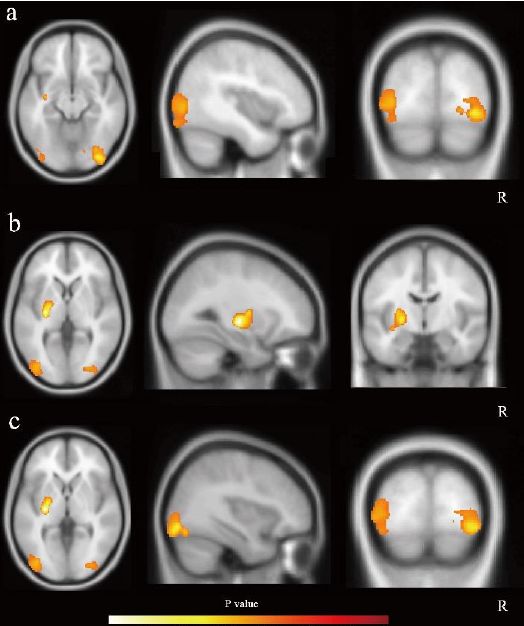

与此同时,宫教授带领的团队,也发现相比于服药前,患者长期服药后,右枕叶、左枕叶以及左侧基底节区的脑灰质体积明显下降(下图黄色符号圈出了受影响的区域);既往研究显示:这些区域的脑灰质与认知功能等重要的大脑功能密切相关。